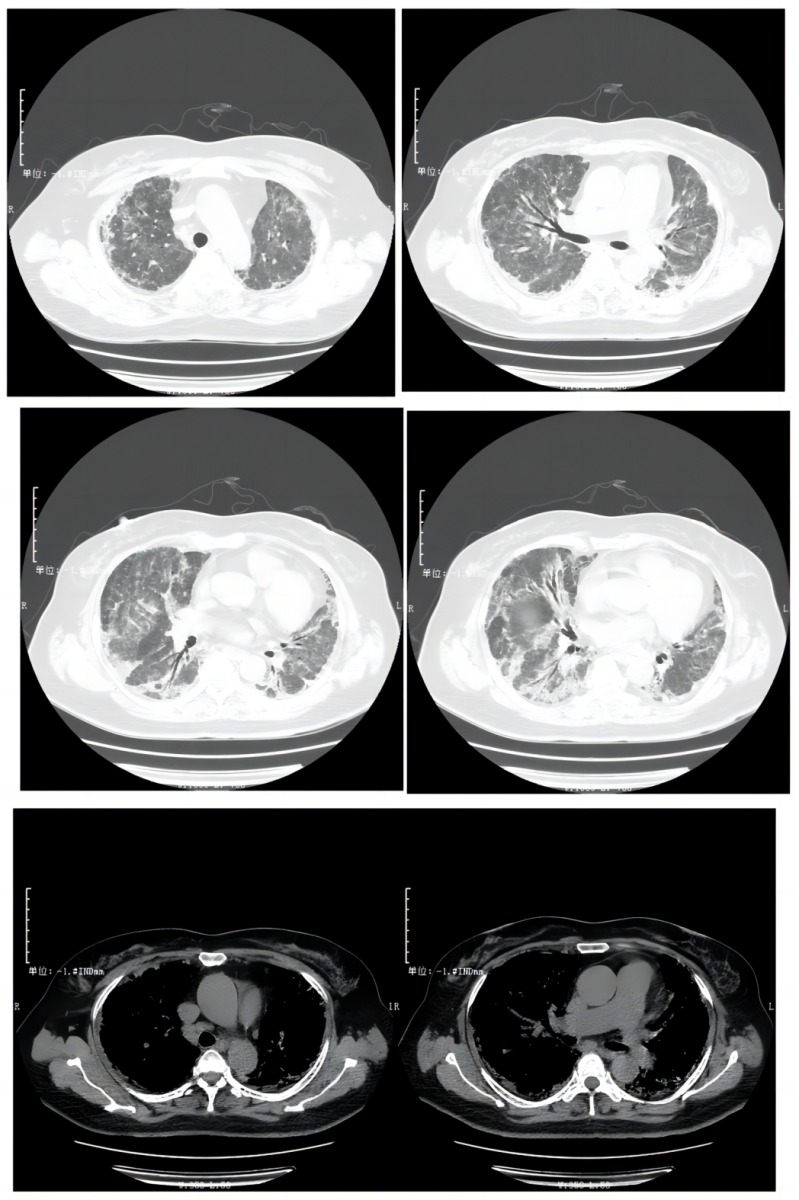

图1. 外院胸部CT